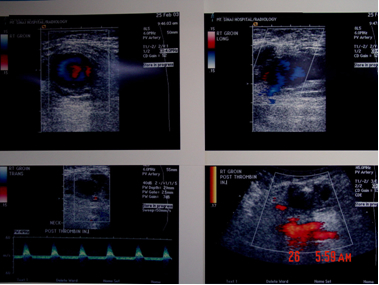

The images below show how I occluded a pseudoaneurysm of the right common femoral artery in a woman who developed one after cardiac catheterization.

The top 2 images show turbulent blood flow in the sac of the pseudoaneurysm, which in the second top image is shown to have a short narrow neck (the blue color below the turbulent sac) demonstrated to connect it to the right common femoral artery. The absence of turbulence in the 2 bottom row images means that the sac is thrombosed; the bright red color behind the sac in the lower second image is the common femoral artery, proving that it was not occluded during thrombin injection into the sac.